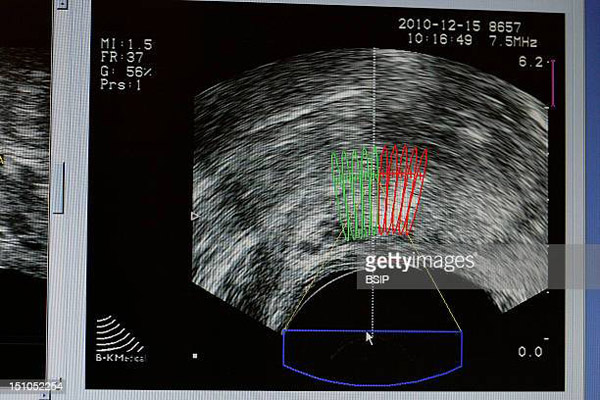

超聲波掃描使用了一種不同于MRI掃描的成像技術(shù),稱為多參數(shù)超聲(mpUSS),它使用聲波來觀察前列腺。該測試需要使用一種帶傳感器的探針來拍攝前列腺圖像,它被放置在直腸中,發(fā)出的聲波會被器官和其他結(jié)構(gòu)反射回來,形成器官的。

研究人員還使用特殊的超聲波成像技術(shù)來觀察組織的僵硬程度和血液供應情況。這些被稱為彈性成像、多普勒成像和微氣泡對比度增強。由于癌癥密度更大,供血量更大,因此顯像效果更清晰。